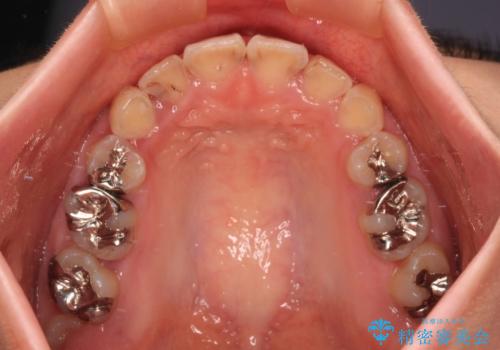

- 上の前歯の出っ歯とでこぼこの歯並びを気にして来院された患者様です。

上下顎歯列ともに前方に突出していましたが、上顎歯列がより前方位にあったため、上顎左右は第1小臼歯を、下顎左右は第二小臼歯を抜歯することとしました。

目立たないワイヤー装置にて抜歯矯正を行うこととしました。